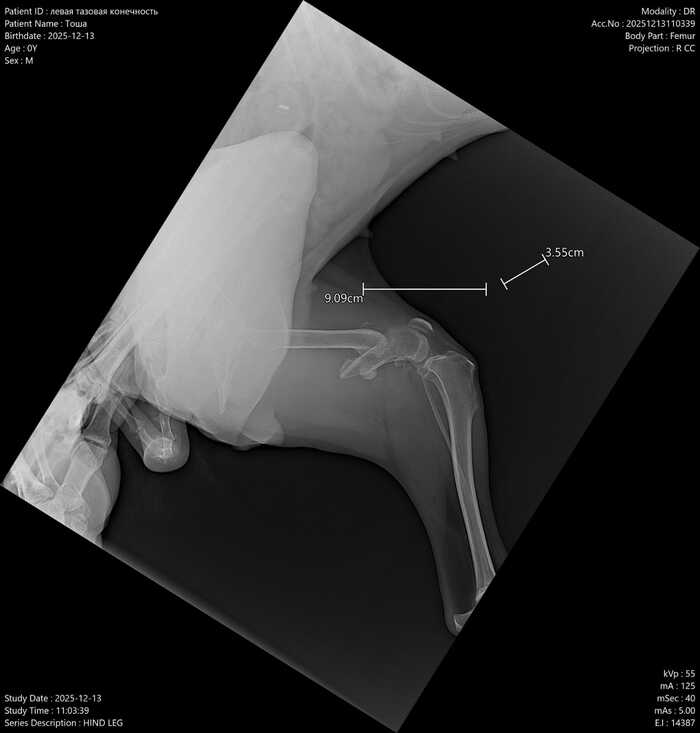

Диагноз: Сложный перелом.

Что нужно: Операция (остеосинтез с пластиной), стерилизация, УЗИ.